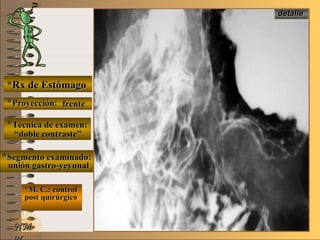

*Rx de Estómago*Rx de Estómago

**Proyección:Proyección:

**Técnica de examen:Técnica de examen:

**Segmento examinado:Segmento examinado:

*M. C.: control*M. C.: control

post quirúrgicopost quirúrgico

NMNM

frentefrente

““doble contraste”doble contraste”

unión gastro-yeyunalunión gastro-yeyunal

A-A-El examen es normal o patológico?El examen es normal o patológico?

Examen patológico de estómago con técnicaExamen patológico de estómago con técnica

de doble contraste, localizada, post quirúrgicade doble contraste, localizada, post quirúrgica

en proyección de frenteen proyección de frente

B-B-La patología es congénita o adquirida?La patología es congénita o adquirida?

Patología adquiridaPatología adquirida

D-D-La misma es neoplásica o no neoplásica?La misma es neoplásica o no neoplásica?

**OpciónOpción

de volverde volver

Patología adquirida orgánica neoplásicaPatología adquirida orgánica neoplásica

E-E-Puede describir la o las imágenes patológicas?Puede describir la o las imágenes patológicas?

Se identifica la anastomosis de la unión gastro-Se identifica la anastomosis de la unión gastro-

yeyunal (Billroth II) lugar donde residiban lasyeyunal (Billroth II) lugar donde residiban las

lesiones neoplásica, se valoran también el diá-lesiones neoplásica, se valoran también el diá-

metro de la “boca” y la integridad de la suturametro de la “boca” y la integridad de la sutura

C-C-Dicha patología es orgánica, funcional o mixta?Dicha patología es orgánica, funcional o mixta?

Patología adquirida orgánicaPatología adquirida orgánica